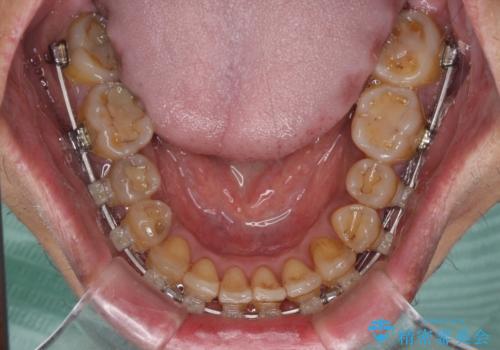

前歯のクロスバイトを改善 ワイヤー装置での非抜歯矯正

- クリアブラケット

- 骨格的な咬み合わせのズレ、前歯のデコボコとクロスバイトを気にして来院された患者様です。

骨格のズレが顕著であると診断され、マウスピース矯正では奥歯の咬み合わせが整えにくいと判断し、ワイヤー装置による矯正治療を行うこととしました。

上下の叢生は速やかに改善できましたが、右側のクロスバイトの改善に1年以上の期間を要しました。